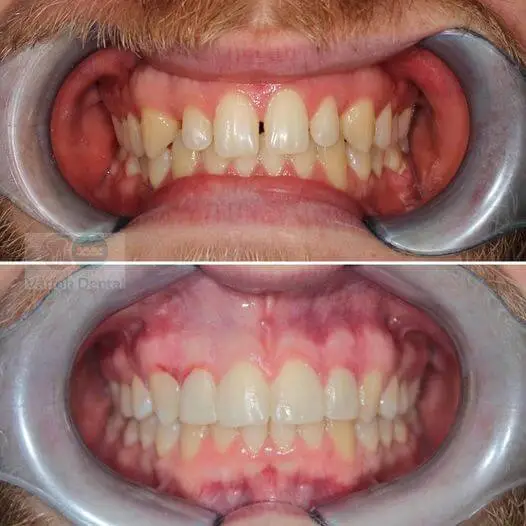

Fogszabályozás

A kezelés célja a torlódás és a keresztharapás rendezése, a csírahiány következtében kialakult foghiány megszüntetése és a szép mosoly kialakítása volt.

A fogászati probléma megoldására a fém fogszabályozó készüléket ajánlottuk mindkét fogívre.

A kezelés kb. 2 évig tartott.

A fogszabályozó szakorvosunk, Dr. Csulak Fruzsina szakértelmének és páciensünk kitartásának eredménye a képeken látható gyönyörű mosoly